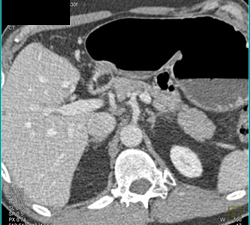

Catheter From Stomach Into Pseudocyst